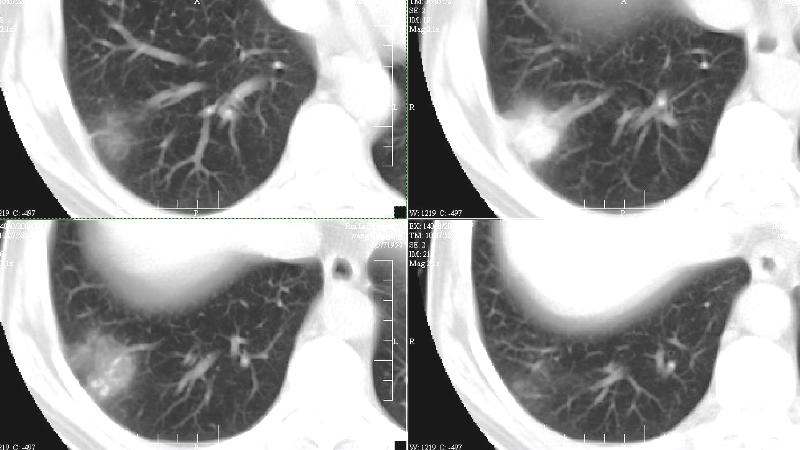

bp:180/120.神清,心肺未见阳性征象。临床高度怀疑肺癌(脑转移)。胸片:右下肺外基底段3.0x3.0cm球形病灶,考虑周围性肺癌。ct:右肺下叶外侧基底段病灶,考虑炎性结节可能性大,其它?建议治疗后复查。

右下叶外基底段炎性假瘤可能性大,建议抗炎治疗后复查。

建议上传颅脑检查综合分析,胸部资料高度提示肺癌可能。

结节型的炎性假瘤、结核球、周围肺ca,就暂时的影像技术来说鉴别还是难点,很难突破

如果抗炎治疗未果,宁切勿留,多做解释工作吧